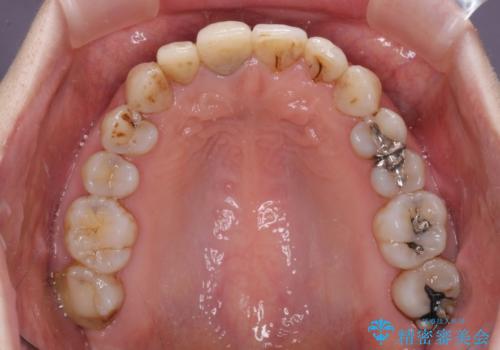

- 前歯の歯並びやむし歯治療の跡、奥歯の銀歯を気にして来院された患者様です。

インビザラインによる矯正治療の後に虫歯や銀歯をセラミックにて補綴することとしました。